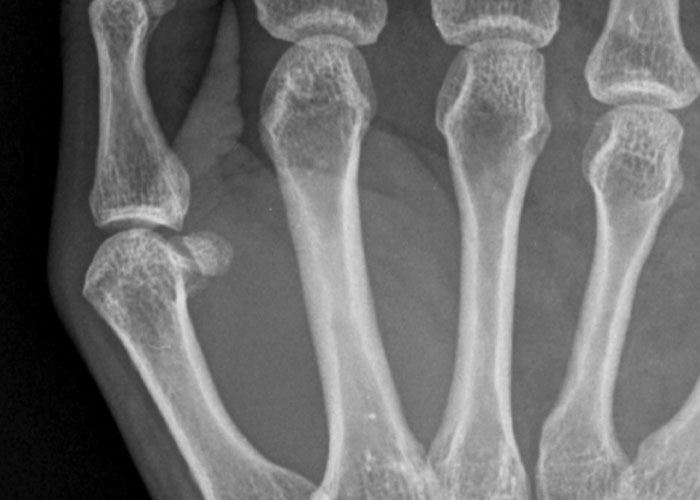

#34

I have offsetting birth defects in my hand. I inherited polydactyl genes from my mom and missing fingy genes from my dad. I have 10 fingers, but they’re not normal.

My right hand has 2 ring fingers and no pinky. Looks almost totally normal til you X ray it.

(Edit- The key difference between your pinky and other fingers is that the pinky shares a ~~knuckle~~ tendon with the ring finger. Thats why you can’t fold your pinky flat without also bending your ring finger in a little. I however can make a fist with only my “pinky” no problem.).